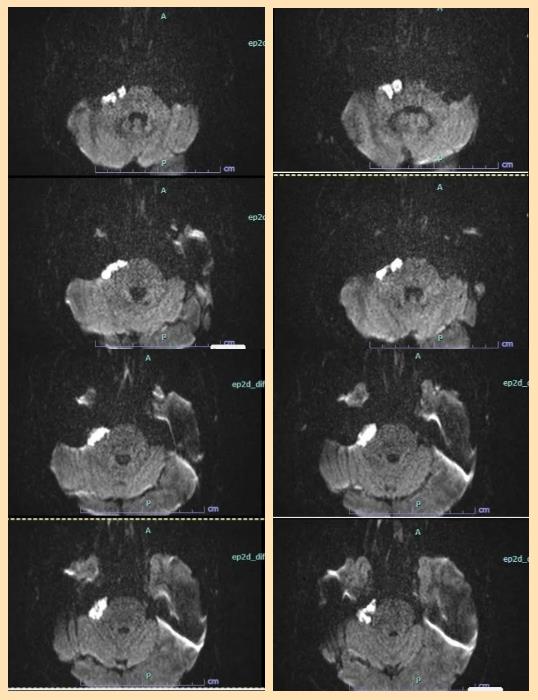

在术前筹备阶段,青海红十字医院神经外科组织本院影像科、麻醉科核心骨干,与济医附院王海涛教授团队通过远程医疗平台开展多轮深度会诊。该院医师详细汇报患者病情、影像资料及初步诊疗思路,结合高原患者生理特点提出诊疗疑问;济医附院专家团队结合丰富临床经验,对手术入路选择、血管神经粘连处理策略及术后并发症防控方案等给出全面指导,最终双方达成共识,确定采用经乙状窦后入路手术方案。

术中探查发现,肿瘤呈珍珠样外观,与脑干腹侧面、小脑前下动脉及多组颅神经粘连异常紧密,剥离空间极度狭小。面对这一突发状况,青海红十字医院手术团队沉着冷静,严格遵循术前既定方案,在顾更诗医师的指导下,运用娴熟的显微外科技术,采取瘤内分块减压、锐性精细剥离相结合的策略,在神经与血管交织的“丛林”中谨慎操作。每一次剥离、每一次止血,都凝聚着两地医者的专业与默契,双方实时交流解剖判断、共同优化手术动作,始终将重要神经血管的保护放在首位。经过数小时的紧张奋战,肿瘤被次全切除(为保护紧密粘连的神经,仅残留极少非功能区囊壁),所有重要神经血管结构完好无损,手术取得圆满成功。